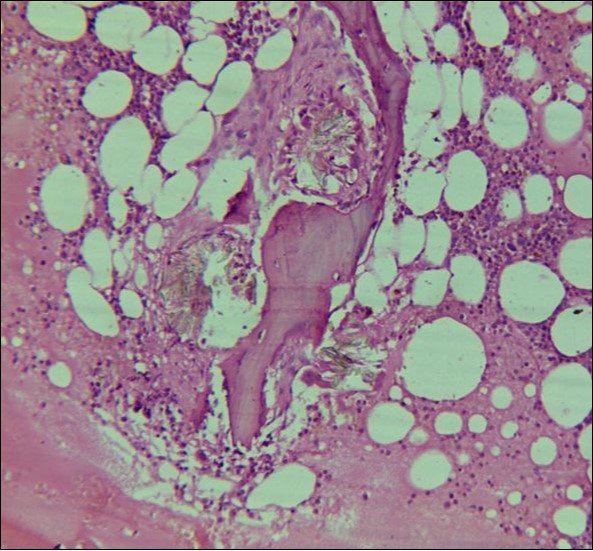

A 24 years old male, presented with the complaints of multiple recurrent renal stones bilaterally. He was on dialysis since last 6 months. His brother had died with chronic renal insufficiency secondary to nephrolithiasis. His routine investigations at the time bone marrow studies revealed anemia with a Haemoglobin of 6.6g/dl, White blood cell count of 5.3 x 109/l; Platelet count of 228 x 109/l. Serum Creatinine was very high 13.9mg/dl. X Ray Abdomen revealed multiple bilateral renal calculi and in addition gall bladder calculi. On ultrasound abdomen his right kidney was 10.5cm x 5.6 cm, had a cyst in the upper pole, multiple calculi were causing hydronephrosis. Left kidney was 8.5cm x 4.8 cm, with multiple calculi. Both kidneys showed increased echogenecity. Serum oxalate levels were 91.2 mg/dl (Normal Range 1-2.4 mg/dl). His Parathyroid MIBI scan was normal, but plasma Parathyroid hormone levels were 373 pg/ml (Normal Range 16 – 87pg/ml). Normochromic normocytic anaemia was present, with normal WBC and platelet count. The bone marrow aspirate was unsuccessful. The trephine biopsy revealed reduced cellularity, depressed erythropoeisis with partly replaced haemopoietic tissue with calcium oxalate crystals (Figure 4) which showed birefringence on polarized light (Figure 5).

Figure 4.Photomicrograph of bone marrow core from case2 showing Para trabecular arrangement of calcium oxalate crystals. Increased fat spaces and depressed erythropoiesis is evident.

Systemic oxalosis can be a primary or a secondary disease. Primary hyperoxaluria Type 1 (PH 1) is due to the deficiency of glyoxylate aminotransferase and Type II due to that of glyoxylate reductase/D-glycerate dehydrogenase. PH 1 is an autosomal recessive disorder characterized by hyperoxaluria, calcium oxalate urinary lithiasis in childhood, nephrocalcinosis and renal failure which in turn leads to high blood oxalate levels and precipitation occurs throughout the body in the skin, blood vessels and joints. Secondary oxalosis occurs due to oxalate-rich diet, increased absorption or production of oxalate and reduced excretion as seen in renal failure. Variable degree of cytopenias or pancytopenia may accompany extensive oxalosis. Bone marrow aspirate may be unsuccessful due to extensive crystal deposition or accompanying fibrosis. Calcium oxalate crystals are well demonstrated on trephine biopsy with associated fibrosis and occasionally granulomas. They have a grey-yellow radial arrangement on hematoxylin and eosin staining and are birefringent under polarized light.4 Liver biopsy is the confirmatory test which demonstrate reduced glyoxylate aminotransferase activity (PH1). Molecular diagnosis, being non-invasive, is preferred, if available.5 An early diagnosis of oxalosis is of immense value, because at a stage when renal failure has not set in, proper management can arrest or at least delay the progress of disease. However, in patients who have already developed renal failure at the time of diagnosis, a combined liver and kidney transplantation offers the only salvation.6